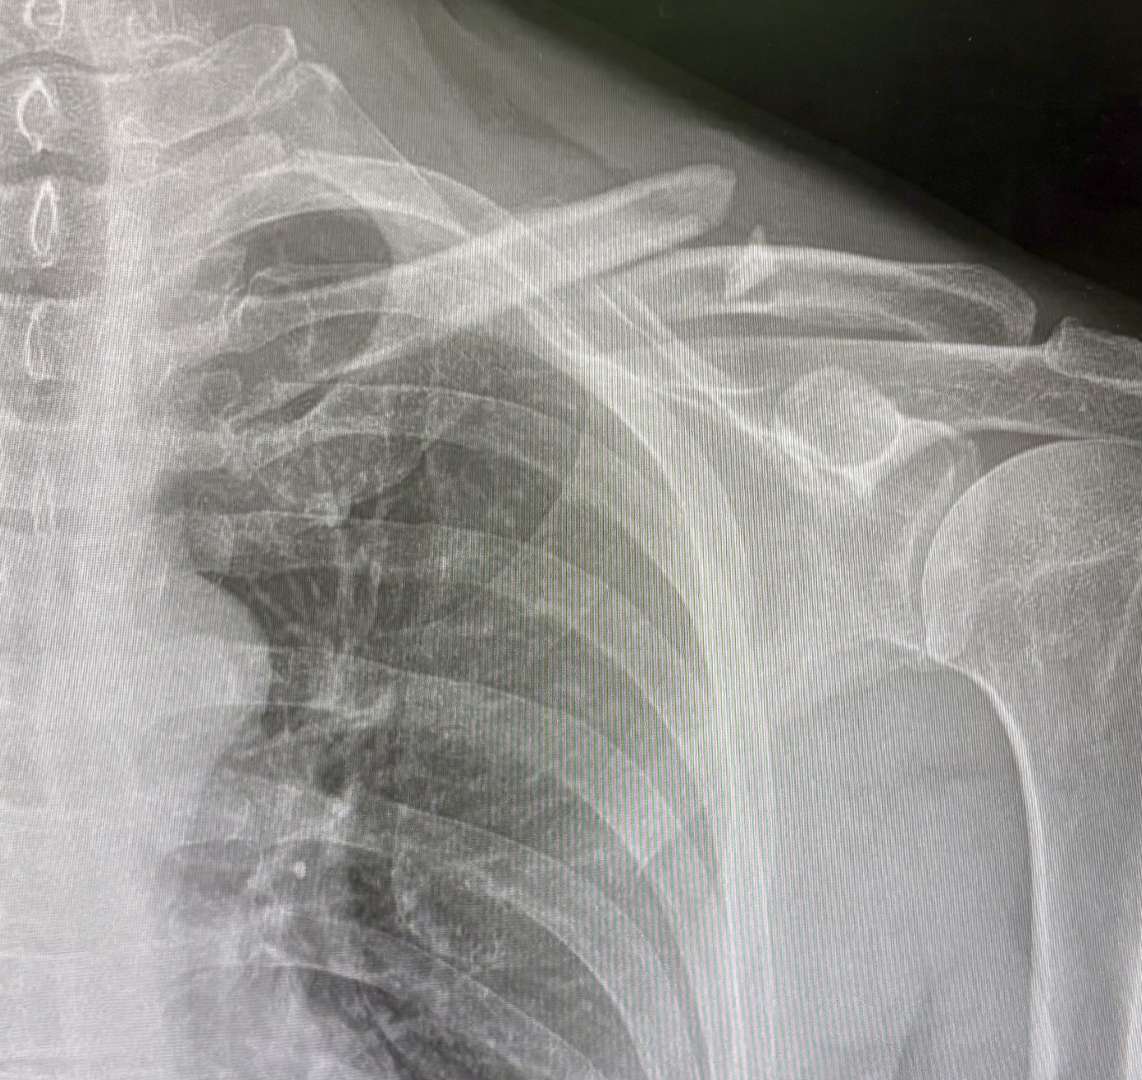

I broke my collarbone on June 20th - a single break at about 45 degree - but one of the bones was left sticking up visibly again the skin (didn’t come through). The end of the bones were 1.5cm apart and showing no sign of moving back together and the NHS were just wanting to “wait and see”.

Luckily I have health cover through work so went to get a 2nd opinion. They said there was an 80-90% chance it would connect the ends by growing bone between them - but that I’d be left with the bone really sticking up. They said you could go that route or you could have it plated together. I opted to have it plated towards the end of July.

Things are progressing steadily - the fracture is gradually filling in on the x rays - but you can still clearly see where it was broken at last x ray (the black line is gradually going mistier on the x ray). I’m now using light stretchy bands to start building up strength in the shoulder after spending a while working on getting a better range of motion in it (all based on instructions from the consultant and a physio).

I’ll add some photos - personally I’m glad I got it plated at this moment in time as everything was moving about prior to having it plated and any kind of transport (bus / car) was jarring it. Immediately after plating this became instantly more comfortable.

That's quite a gap! I can see why you had it plated. Mine never hurt amazingly until the AC joined the party. It did grind a bit for the first week but then stablilised. That image is when I did it and about 7 weeks in where you can see new bone but it's very gray (soft).